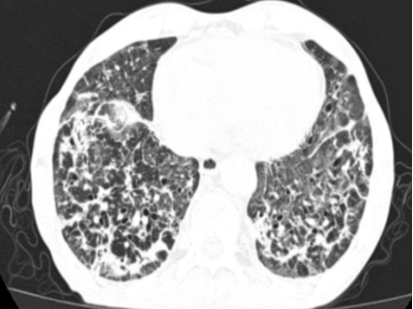

关键的tNGS检测结果揭晓了幕后真凶,耶氏肺孢子菌、巨细胞病毒、EB病毒及黑曲霉混合感染。至此,诊断完全明确,这是一例极为罕见的、在非HIV患者身上发生的PJP合并多种病原体感染,并叠加肺栓塞和呼吸衰竭的极危重病例。

在接下来的救治过程中,挑战接踵而至。患者相继出现了血痰、血便、顽固性的低钠血症和心脏早搏等问题,治疗团队如同闯关一般,对每一个新情况都及时研判并调整用药策略。随着治疗的深入,患者的体温首先恢复正常,成为病情好转的曙光。之后的复查CT显示,肺部炎症开始逐步吸收。虽然过程中出现了肺纤维化的迹象,但通过加用抗纤维化药物尼达尼布,这一进程也得到了有效干预。